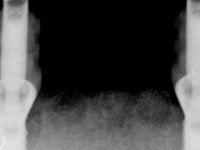

Female patient, 57 years-old, non-smoker, with a full denture in the maxilla and a removable partial denture in the mandible. Teeth 43-41-41-31-32 were indicated for extraction. Posterior sectors of the mandible presented significant bone resorption.

Two dental implants were planned in the CBCT scan, in the area of the inferior canines. The dental extractions were performed and, simultaneously, the alveolar crest was flattened and the implants were placed. Three issues were considered while implant placement: parallelism of the axis, same height of the implant’s neck, and same position in the coronal plan. This 3D insertion is essential to have a good retention of the overdenture in the future. Patient’s removable denture was fixed in the dental lab, to include the extracted teeth, and a soft-tissue relining was done over the healing abutments. After the osseo-integration period, a first impression was done with an open-tray and a doble-mix technique. This dental impression allowed the production of screwed wax-rims and an individual tray for a functional impression. A second impression, final, was done with an individual tray with a monophasic silicone. The occlusal wax-rims were correct in the mouth according to the full denture guidelines. Special care was taken with the occlusal vertical dimension and the support in the soft-tissues. A silicone bite registration material was used to better defined the intermaxillary relations. Teeth set-up was done in the dental lab with the selected tooth color. Due to the fact that the base was screwed to the dental implants, the teeth set-up was functionally evaluated in the mouth. Another silicone bite registration material was used to allow final occlusal adjustments. Finally, the locators were screwed and the retention nylons were selected according to the patient needs.